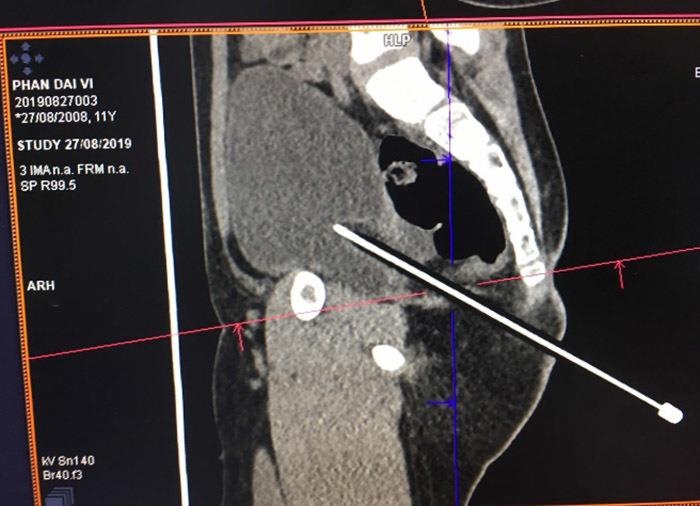

Theo đó, hôm 27/8, bé trai được đưa vào Bệnh viện Nhi Đồng Cần Thơ trong tình trạng bị một cây bút chì đâm vào vùng cạnh hậu môn - mông phải. Ngay lập tức, bé trai này được sơ cứu, cho chụp cắt lớp vi tính bụng chậu và các xét nghiệm cần thiết.

| Bút chì đâm vào hậu môn thấu bụng bé trai. Ảnh: Vietnamnet. |

Qua dựng hình trên phim, bệnh nhi được chẩn đoán vết thương phức tạp vùng cạnh hậu môn - mông phải, nghi ngờ thấu bụng và chuyển mổ cấp cứu.

Khi nội soi vào ổ bụng, bác sĩ phát hiện một lỗ thủng tại Duoglas, kích thước khoảng 1x1,5 cm, độ sâu của bút chì đâm xuyên khoảng 15 cm.